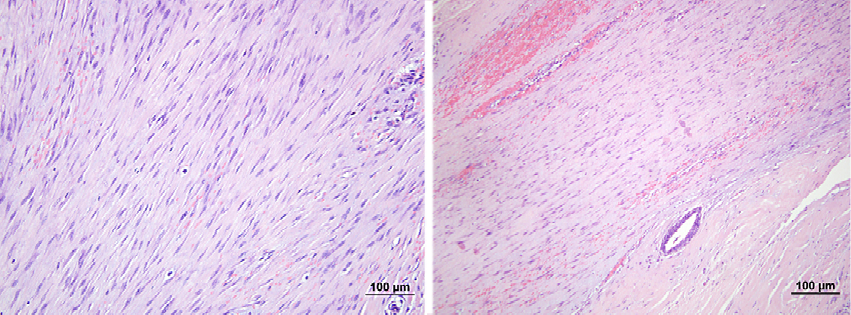

During physical examination a 2 cm hard, not tender, with ill-defined margins lump in the upper inner quadrant of the right breast has been found. There was no nipple retraction, discharge or skin change. A breast ultrasound showed a 1.24x0.85 cm suspicious ill-defined hypoechogenic lesion at 1 o’clock position of the right breast (Figure 1). Mammogram revealed a local hyperdense zone in the right breast (Figure 2). Histopathological examination of the tumour core biopsy material revealed desmoid type fibromatosis. The patient underwent wide local with clear margins excision of the lesion. Histopathological examination of surgical material confirmed desmoid type fibromatosis (Figure 3). Tumour was poorly demarcated, composed of spindle-shape myofibroblasts arranged in long sweeping fascicles. There was no mitotic activity. Immunohistochemical findings of the mass showed a focally positive reaction with beta-catenin, and a negative reaction for CD34, Desmin, CK. The patient did not require any adjuvant treatment. There was no recurrence after two years of follow-up.

Fig. 3. Microscopic pathological findings revealed spindle cells among collagen depositions (HE staining)

Clinically and radiologically diagnose desmoid tumour of the breast is difficult because it may mimic breast carcinoma [3, 4]. Conclusive diagnose is made just after histopathological examination of the lesion. Macroscopically the lesion appears as greyish-white, firm consistency, irregular, nodular mass [1, 6]. Microscopically spindle cells are seen with varying amount of collagen fibres deposition [2, 7]. Immunohistochemistry is positive for vimentin, actin, but negative for desmin, cytokeratin, S-100, CD 34 [1, 5, 7]. Histopathologically desmoids tumour must be differentiated from the scar formation, fibrosarcoma or fibromatosis – like metaplastic spindle cell tumour [2].